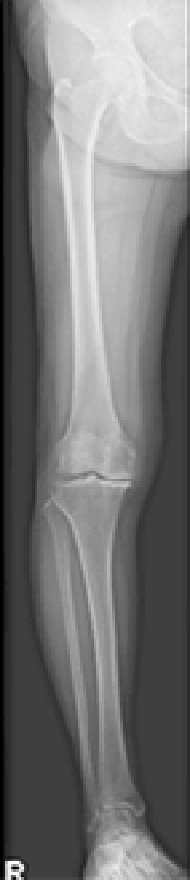

デジタルX線テレビシステム

従来より高画質で低線量なデジタルX線テレビシステムです。透視検査では人体の透過像を動画で観察し、X線写真を撮影します。消化器から整形外科まで幅広い領域の画像検査に対応しています。